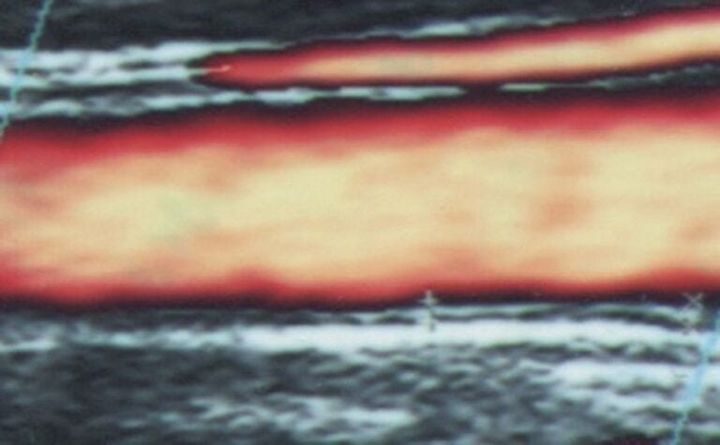

正常な血管

プラークが生じた血管

血管内皮細胞が傷ついて血管内膜に異物が潜り込み、プラーク(こぶ)ができるのが動脈硬化。プラークが大きくなることで、血液の通り道が狭くなります。またプラークは非常にもろく、一部が破れると血の塊である血栓ができ、血管を詰まらせる原因となります。